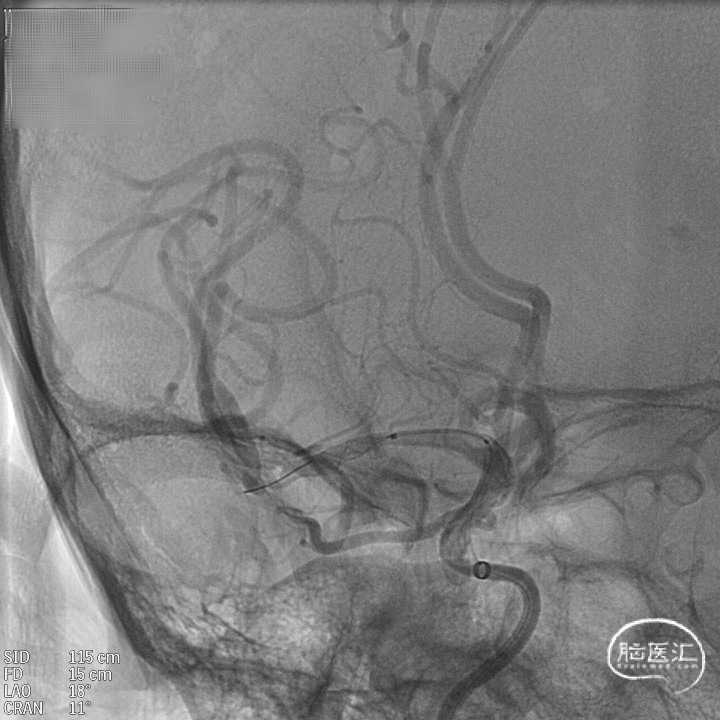

术后造影:支架覆盖两枚动脉瘤瘤颈,贴壁良好,瘤体内可见造影剂滞留。

术后支架显影:

术后造影:支架充分覆盖动脉瘤瘤颈,贴壁良好,瘤体内可见造影剂滞留。

术后支架显影:定位精准,未覆盖颞前动脉及大脑前动脉。